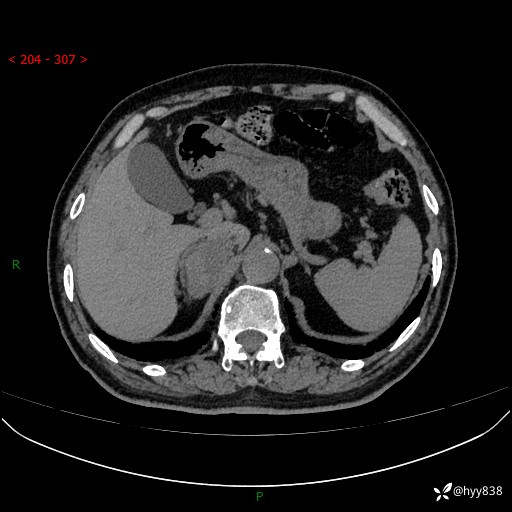

【患者信息】:76岁/男

【主诉】:检查发现右侧肾上腺占位6天

【现病史及既往史】:患者6天前体检发现右侧肾上腺占位,无腰痛,无放射痛,无尿频、尿急、尿痛及肉眼血尿,无畏寒、发热,无恶心、呕吐,今为求进一步治疗,遂来我院就诊,门诊拟“右侧肾上腺占位”收住入院。 起病以来,患者精神、饮食、睡眠可,大小便如常,体力体重无明显变化。

【检查】:肾上腺CT平扫+增强